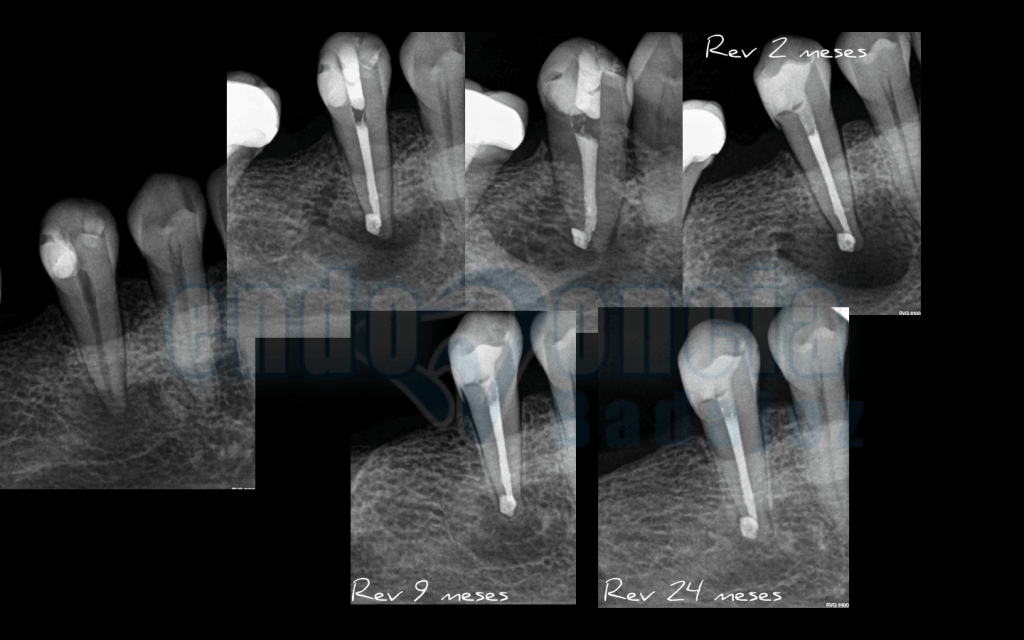

Caso 4:

Premolar inferior, con una periodontitis Apical Asintomática, en el que hacemos un control a los dos años, y vemos una perfecta curación. A los 2 meses tuve un flare-ups.